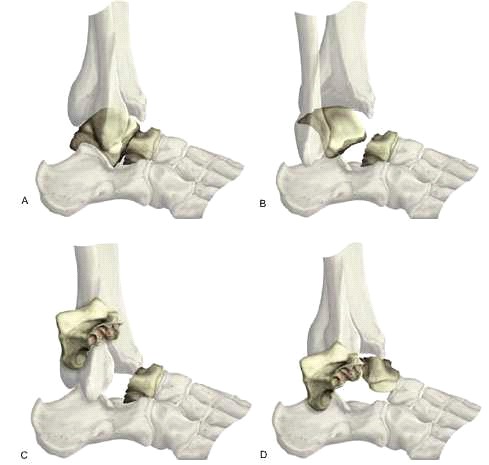

Clasif. Hawkins: para fracturas de astragalo:

- Fractura no desplazada

- Desplazada con subluxacion de articulacion subastragalina

- Desplazada con luxacion subastragalina y del tobillo

- Luxacion adiccional de la astragaloescafoidea